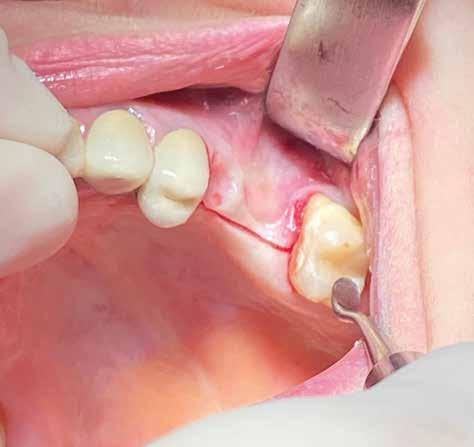

In ultimo, ha grande importanza anche il momento della sutura, la scelta dell’ago, del filo e la tecnica di legatura dei nodi (fatti alla giusta distanza gli uni dagli altri e con la giusta tensione); la riuscita dell’intervento dipende anche dalla qualità con cui vengono riavvicinati i lembi in modo da non ischemizzarne o danneggiarne i bordi. (Figg. 9-14)

Una incisione lineare netta si estende coinvolgendo minimamente il dente mesiale e maggiormente in direzione distale, consente di evitare l’esecuzione di incisioni di scarico che provocano una interruzione della vascolarizzazione maggiore, senza ridurre la visibilità del campo operatorio.